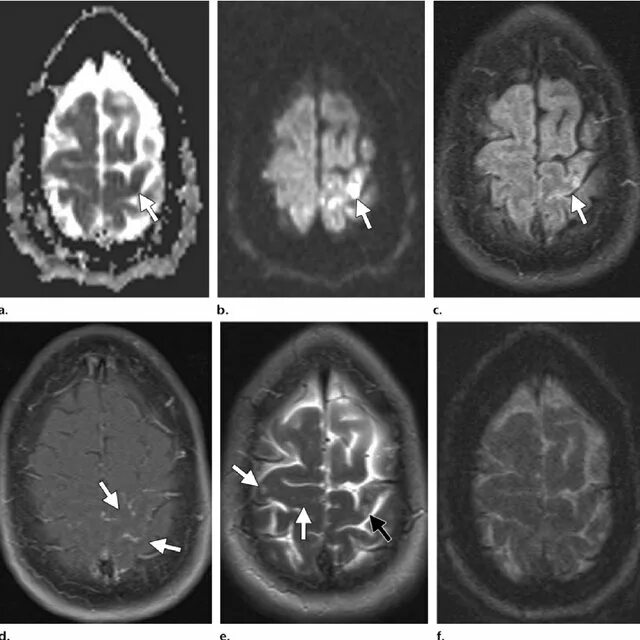

Мрт симптомы